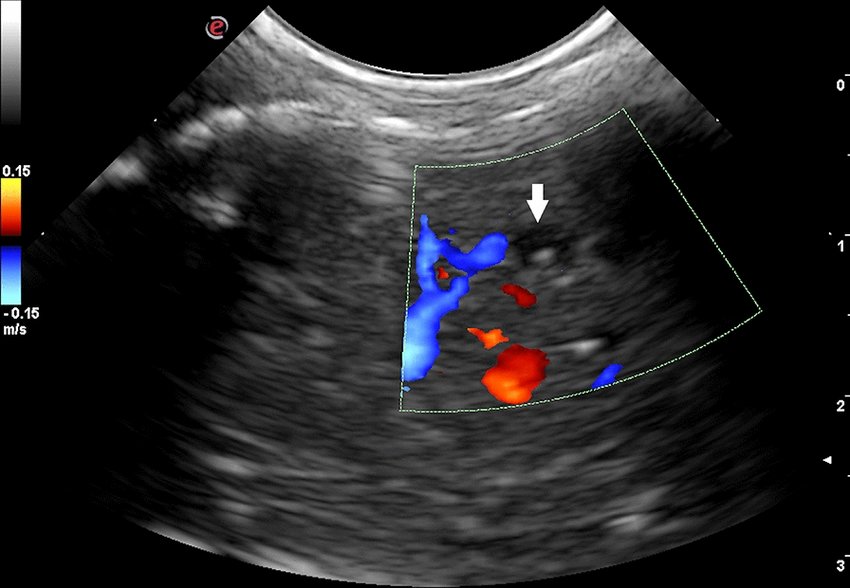

Color Doppler ultrasound is a non-invasive imaging test that evaluates blood flow in arteries and veins. It helps detect blockages, narrowing, or abnormal flow patterns in vessels, making it crucial in the diagnosis of conditions like deep vein thrombosis, varicose veins, peripheral arterial disease, or carotid artery disease.